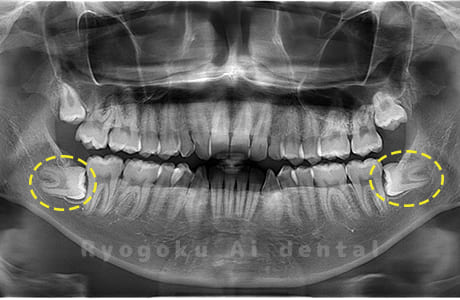

Case02

- 原因

- 下顎の水平埋伏智歯

- 治療内容

- 下顎の水平埋伏智歯を抜歯

<リスク・副作用>

手術後は痛み、腫れ、痺れなどの副作用が生じる場合があります。